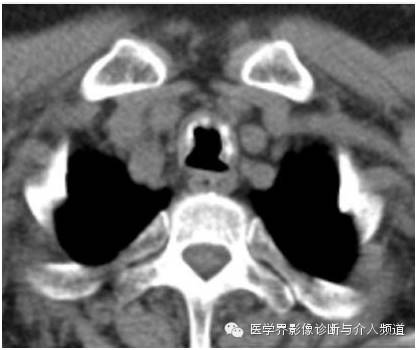

胸部CT平扫显示主支气管前壁及两侧壁可见多个钙化及未钙化的结节,后壁未见异常病变。支气管镜检如上图。

CT主要表现为在气管支气管前壁和侧壁黏膜下散在或多发分布斑点钙化状小突起,突向管腔,大多数突起直径在 1~3 mm,但有的结节较大,达到10 mm。一般黏膜下高密度钙化状影和气管环不连接。

TO病变严重时,气管壁弥漫增厚,管壁塌陷,管腔缩小。当病变发生在叶支气管或段支气管时,常导致管腔狭窄,加上黏液栓塞,极易引起肺不张。病变主要发生在气管中、下段的前、侧壁,后壁一般不累及。但也有文献报道后壁也可见,主要发生在较严重的病例。